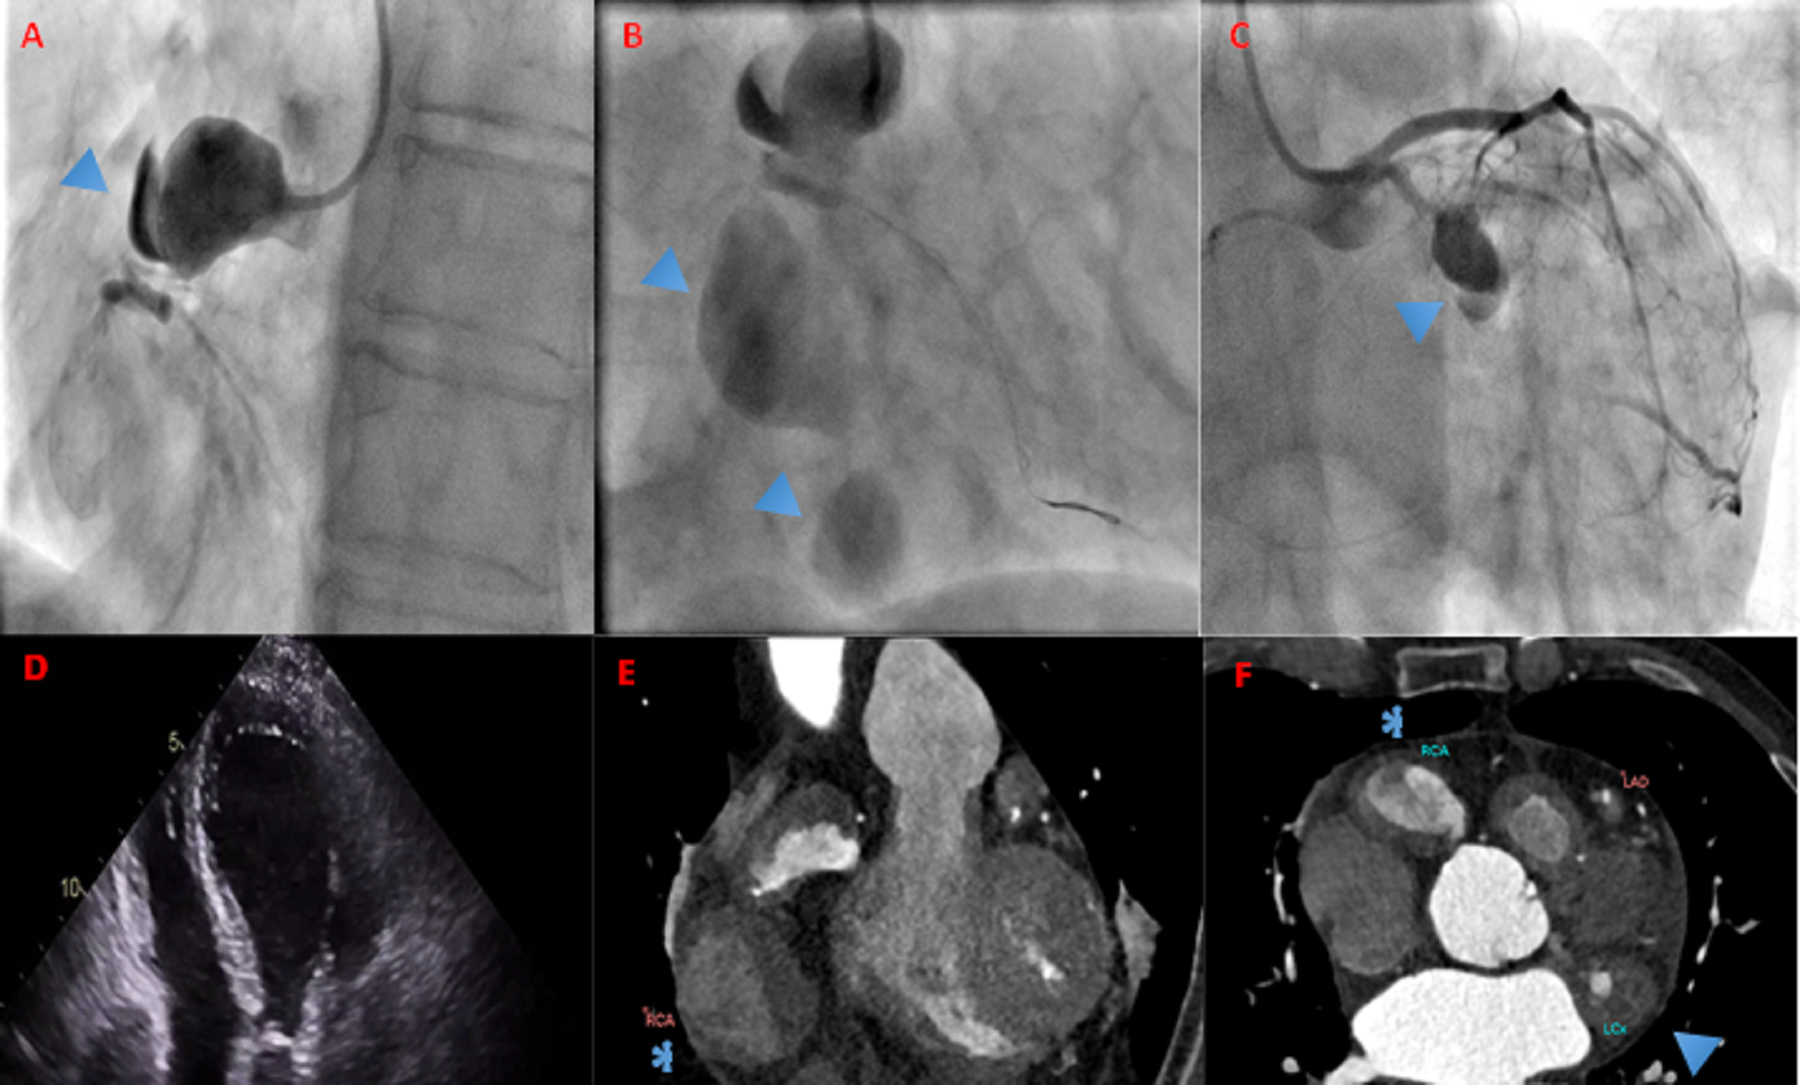

A 77-year-old man presented with an acute inferior ST-segment elevation myocardial infarction. Peak troponin was 26 times higher than normal, and echocardiography showed impaired left ventricular (LV) systolic function; the ejection fraction (EF) was 40%. An emergent coronary angiography demonstrated a large right coronary artery (RCA) proximal aneurysm with an acute occlusion at the neck (Figure).

The occlusion was crossed with a Fielder XTA wire (Asahi) with the help of Supercross microcatheter (Teleflex). Following balloon pre-dilation at the neck, 2 further large aneurysms were visualized. The left anterior descending (LAD) artery demonstrated mildly diffuse disease throughout the vessel, and the left circumflex artery (LCX) had a mid-vessel chronic total occlusion with another proximal aneurysmal segment.

Figure. (A) Angiogram of the RCA with a large proximal aneurysm (triangle). (B) Following balloon angioplasty to aneurysm neck, 2 further aneurysms are visualized (triangle). (C) Pre-stenotic aneurysm of the LCX (triangle). (D) Echocardiogram showing RCA aneurysm and small localized pericardial effusion (asterisk). (E) CT coronal section demonstrating RCA aneurysm (asterisk). (F) CT transverse view demonstrating RCA (asterisk) and LCX (triangle) aneurysms. CT = computed tomography; LCX = left circumflex artery; RCA = right coronary artery.